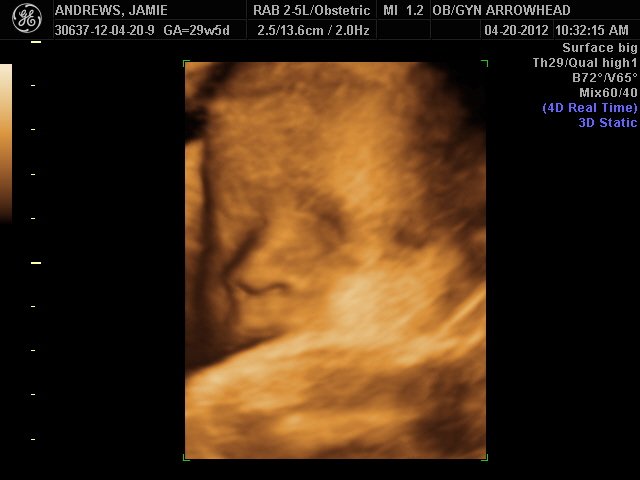

We offer complimentary 3D/4D Ultrasounds to all our OB patients around 30 weeks! The following photos are some examples of our work, shown with permission from our patients.